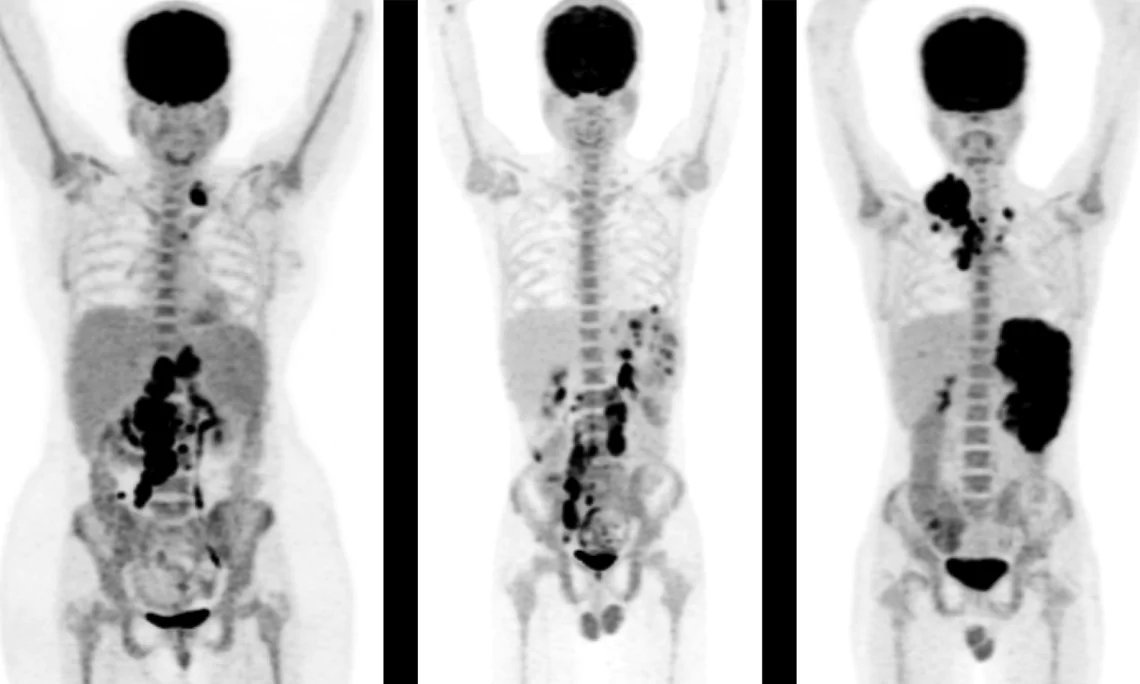

PET (Position Emission Tomography) is a nuclear medicine technique for evaluating biomedical and physiological processes in the body. The combination with CT scan adds anatomic information.